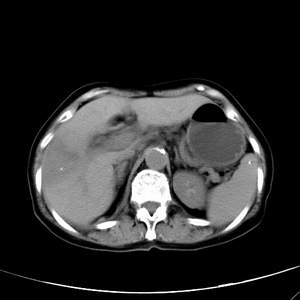

患者,女性,77岁,右上腹胀痛月余。afp正常。ca125升高。即往无肝炎病史。

肝右叶病灶是胆管细胞癌吗?门静脉右支癌栓形成?右侧肾上腺有问题吗?

最后5幅图片是延时7分钟的。门静脉右前支内有充缺吗?如有,肝血管瘤不好解释。

病灶渐进性向心性强化,延时病灶中心见条片状高密度影,局部见肝包膜回缩征,结合病人无肝炎病史,考虑肝右叶胆管细胞癌,门脉右支癌栓形成。